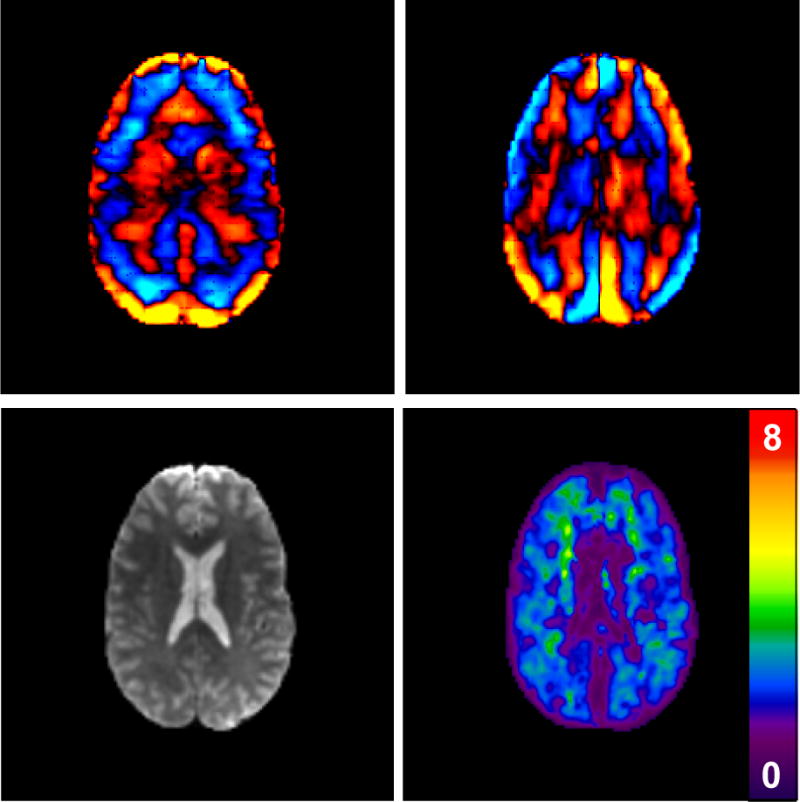

Figure 7 presents MRE data from a healthy volunteer, where a pressure-activated driver was used to introduce 60-Hz shear waves into the brain. In Figures 7a and 7b, x- and y-components of the resulting curl-filtered wave data (processed to remove long-wavelength longitudinal waves) are shown. The magnitude image and corresponding elastogram are shown in Figures 7c and 7d, respectively, demonstrating that quantitative measurements of brain stiffness are possible with MRE. Ongoing investigations in this area will likely determine the viability of MRE to assess specific diseases of the brain, such as the diffuse changes in neural tissue due to aging, stroke, multiple sclerosis and the accumulation of amyloid plaques in Alzheimer’s disease [XX refs].

Figure 7.

MRE of the brain.